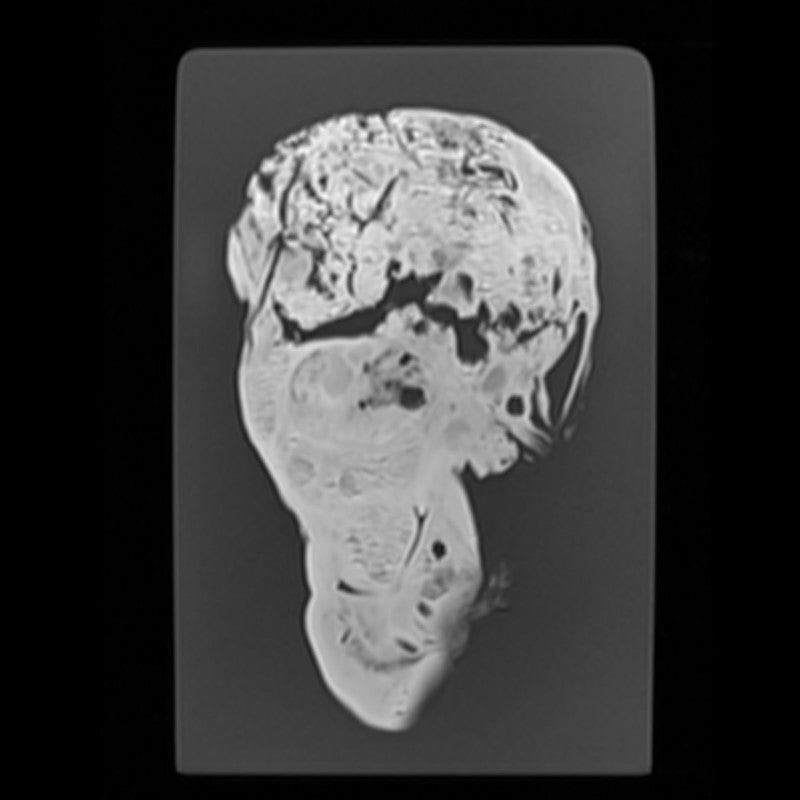

Kidney - Calculous Hydronephrosis